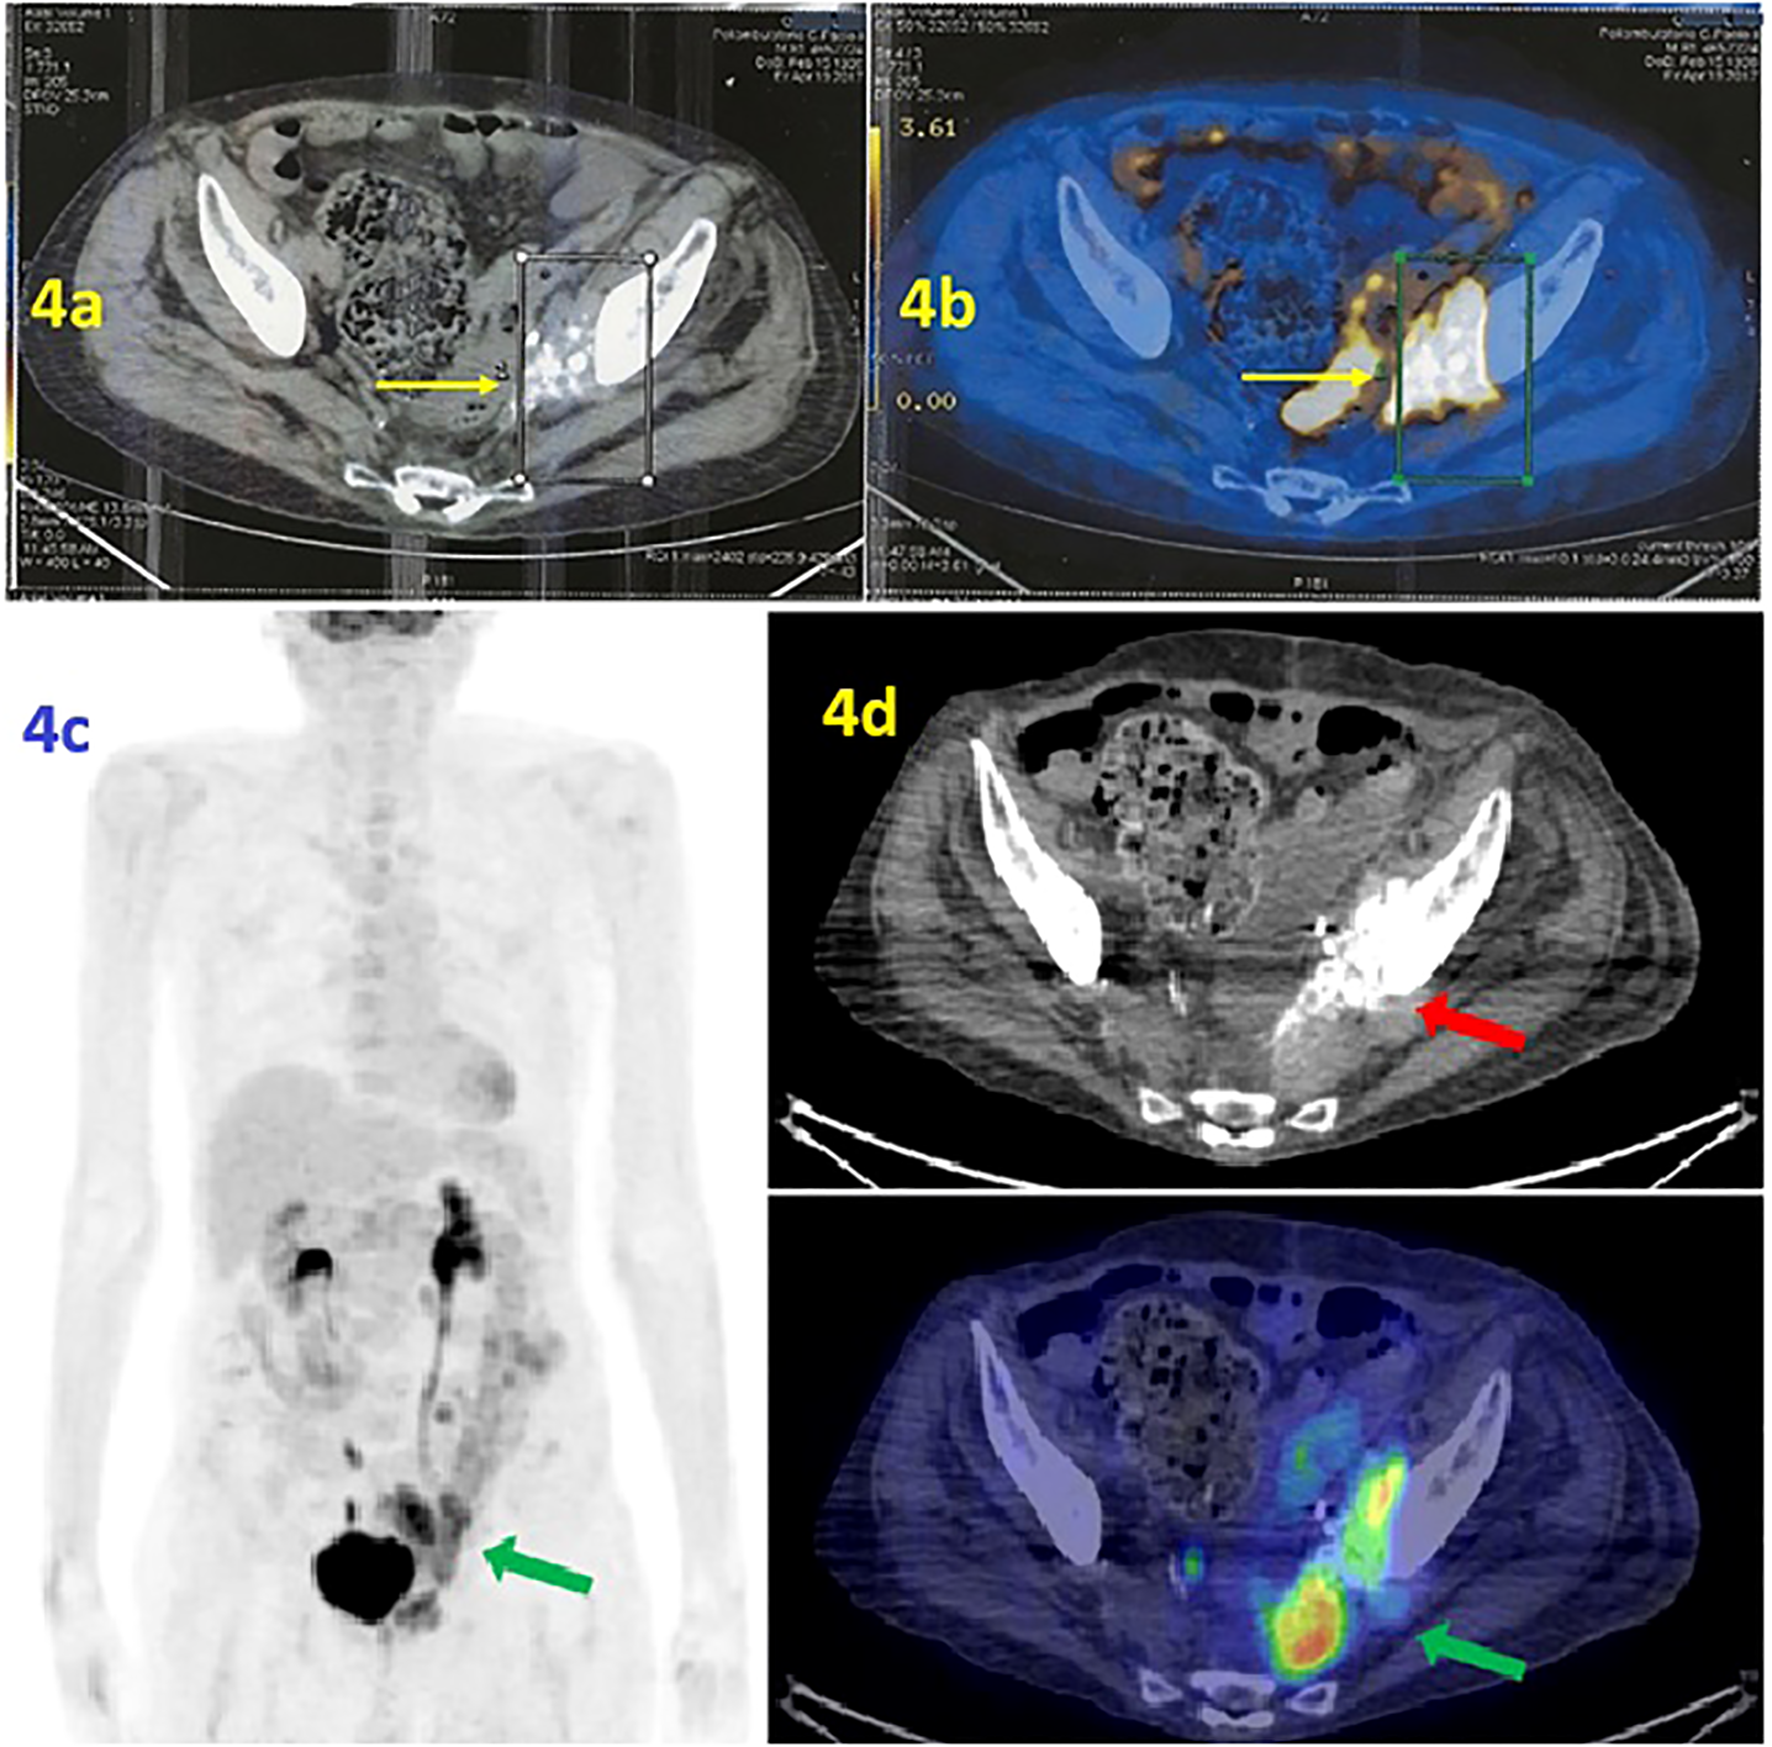

In the first half of 2017, the PET/CT scan showed a progression of disease (PD) consisting of increased uptake of radiopharmaceuticals (Figure 4a). At the same time, the co-registration CT scan documented the volumetric increase of the tumoral mass, from 4 to 6 cm, at the left perivesical site of the pelvis. Please note the characteristic psammomatous bodies in the lesion (Figure 4b).

Figure 4

(a, b) PET scan/CT scan. (a) The PET scan (performed at IRCCS Casa Sollievo della Sofferenza Foundation in April 2017) shows radiopharmaceutical hyperaccumulation in the left area of the pelvis with an mSUV of 10.1. (b) Co-registration CT scan documented the volumetric increase of lesion. Note the psammomatous bodies, a typical marker of ovarian tumors such as adenocarcinoma of Mullerian origin. (c, d) [18F] FDG PET/CT MIP reconstruction and transaxial images (performed at the University Hospital of Bari in June 2019) showed the presence of a tumor lesion in the area near the left side of the bladder, adjacent to the obturator muscle and extended anteriorly to the bladder with an mSUV of 12.5 (green arrow). The psammomatous bodies are evident, a marker of ovarian tumors that confirms the tumor’s Mullerian origin (red arrow).

Therefore, the second line of chemotherapy with carboplatin AUC 3.5 mg/mL per minute plus gemcitabine 800 mg/m2 was administered at the Integrative Medical Oncology Unit of IRCCS Istituto Tumori Giovanni Paolo II of Bari (Italy). Thus, the patient experienced a PFS of 3.5 years. In June 2019, PET/CT showed PD due to an increased radiopharmaceutical uptake at the target lesion (mSUV of 12.5) (Figures 4c, d).